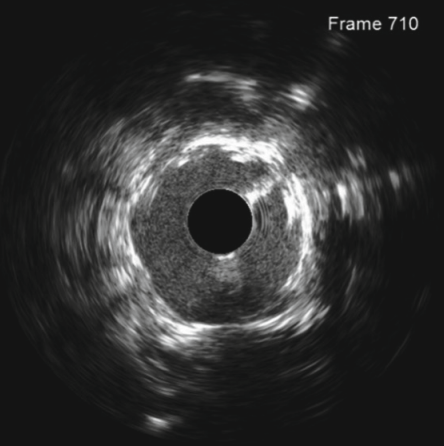

Feature Selection for Malapposition Detection in Intravascular Ultrasound-A Comparative Study

Satyananda Kashyap, Neerav Karani, Alexander Shang, Niharika D’Souza, Neel Dey, Lay Jain,

Ray Wang,

Hatice Akakin, Qian Li, Wenguang Li, Corydon Carlson, Polina Golland, Tanveer Syeda-Mahmood

2nd Intl. Workshop, AMAI, 2023

paper

Provides a comprehensive study on malposition detection using deep learning approaches and proposes a new approach for malposition classification using Mask-RCNN and SWIN transformer.